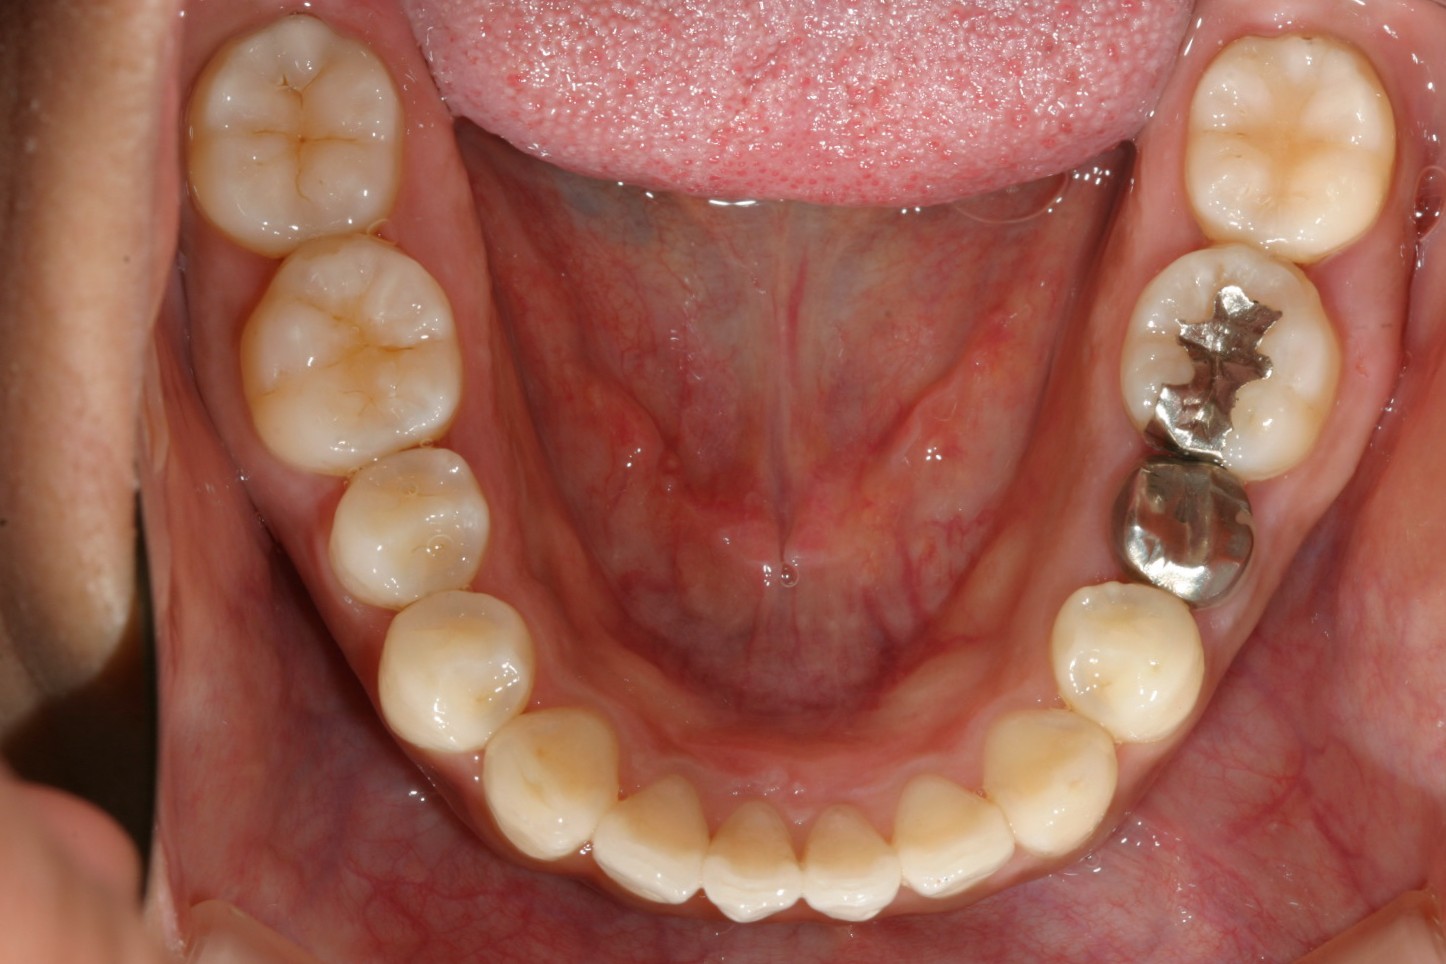

下顎にも僅かな叢生が見られます。

下顎の綺麗ですね~